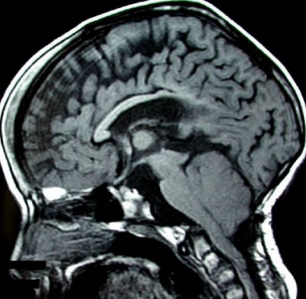

圖2 矢狀位 T1 加權(quán)腦像顯示腦脊液循環(huán)的主要阻塞部位:導(dǎo)水管狹窄及第四腦室腦室層面的消失;橋前池囊性擴(kuò)張;后顱窩結(jié)構(gòu)擁擠;蛛網(wǎng)膜下腔層面枕骨大孔阻塞。